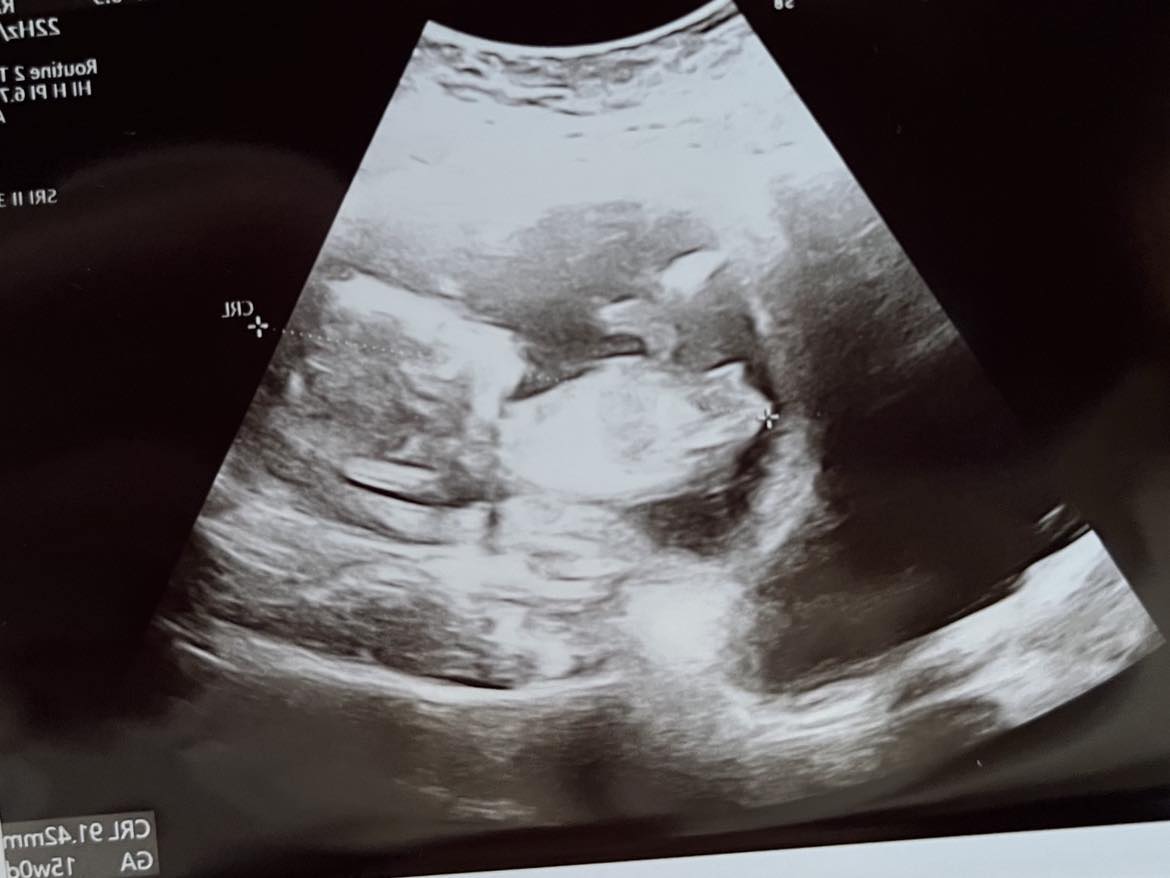

Wyrostek płciowy na usg

Hej dziewczyny! Jak Wam się wydaje chłopiec czy dziewczynka? :D Zdjęcie słabej jakości ale wydaje mi się że widać "wyrostek" - chyba że się mylę o_O

To ja też zapytam , chociaż od lekarki jakieś sugestie były.